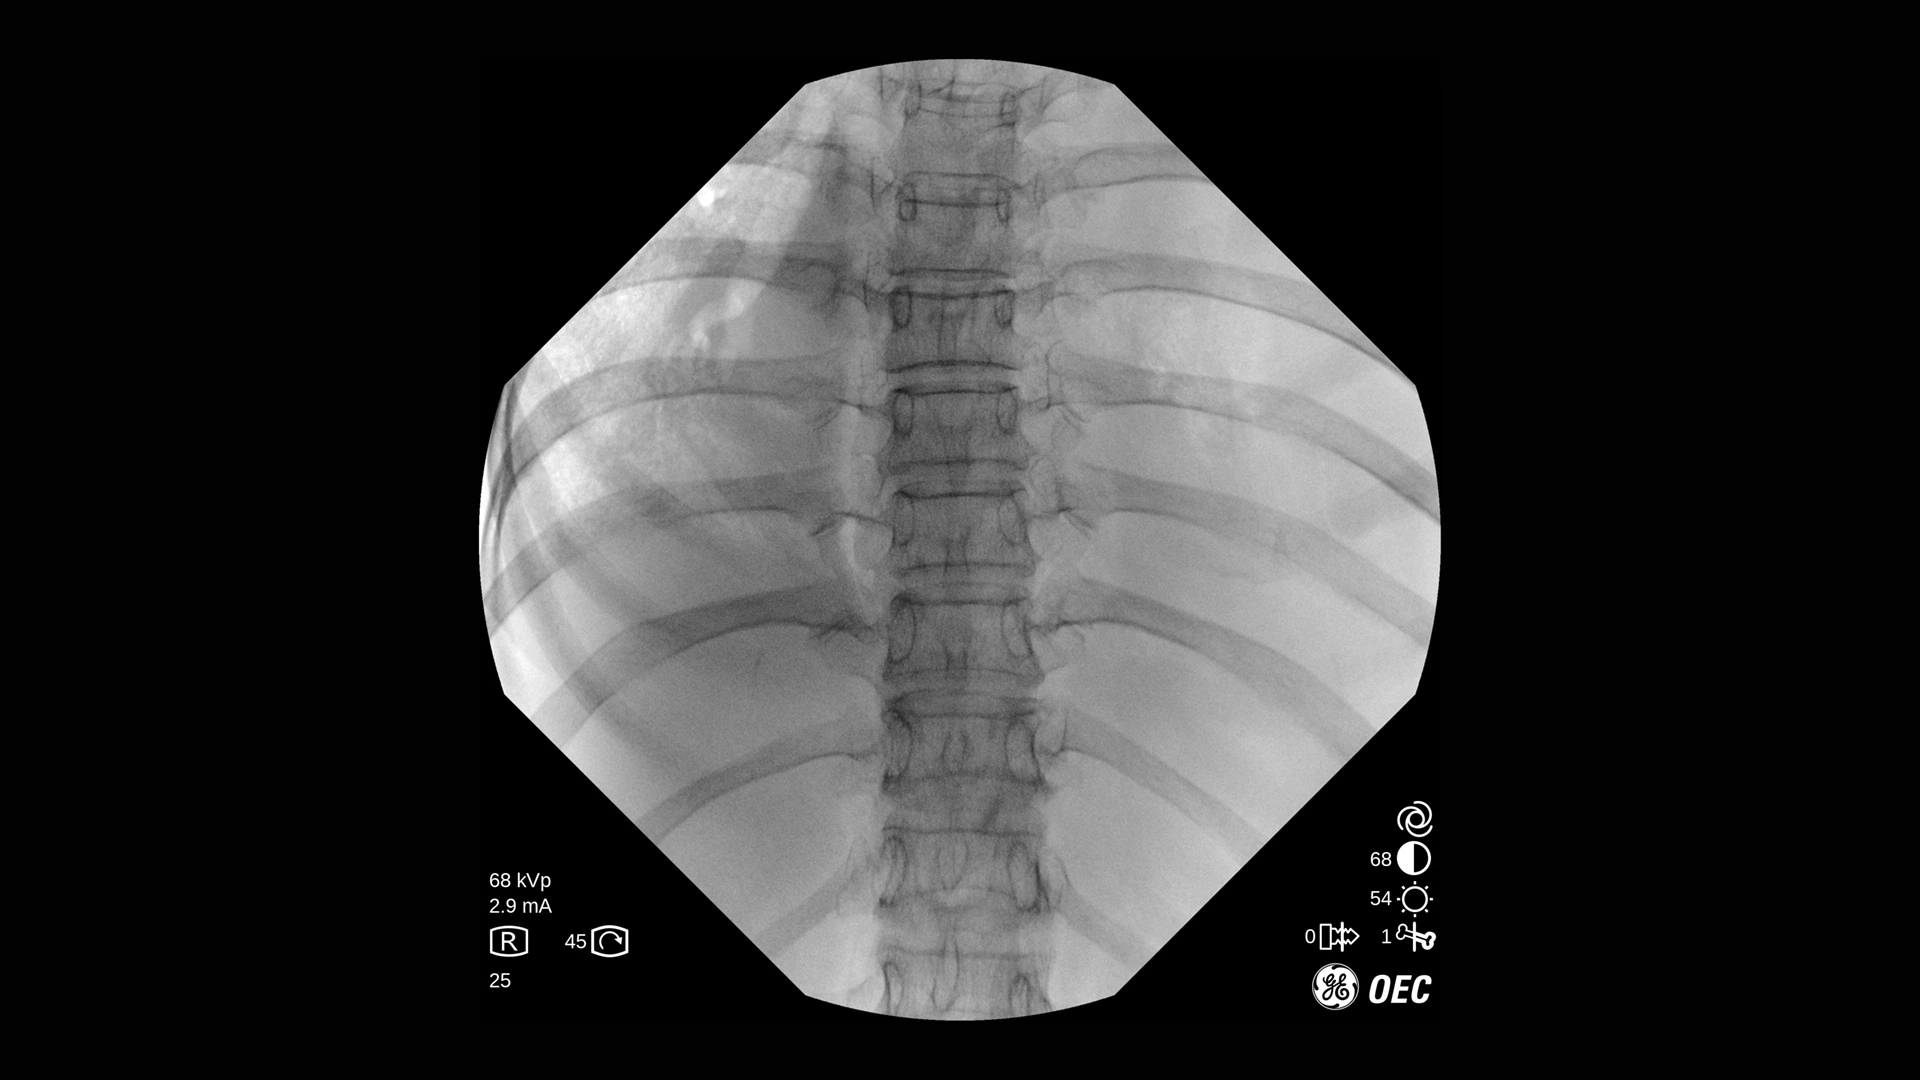

GE Healthcare OEC One CFD относится к классу мобильных рентгеновских аппаратов с С-образной дугой, в которых все ключевые узлы — излучатель, детектор, монитор и панель управления — объединены в единую компактную конструкцию. КМОП-плоскопанельный детектор и фирменная цепочка обработки Clear View обеспечивают высокую детализацию изображения в широком спектре клинических задач: от рутинных травматолого-ортопедических вмешательств до эндоваскулярных процедур и сложной спинальной хирургии. Интеллектуальные алгоритмы подавления помех от металлоконструкций, автоматической оптимизации окна и уровня, а также режимы увеличения позволяют уверенно визуализировать мелкие структуры, проводники и импланты без существенного роста дозовой нагрузки.

- Специализированные клинические профили для ортопедии, спинальной хирургии, общей хирургии, урологии, сосудистых и болевых процедур.

| Низкодозовая рентгеноскопия | Снижение лучевой нагрузки при длительных рентгеноскопических исследованиях и повторных проверках положения имплантов. |

| Импульсная рентгеноскопия | Формирование изображения серией импульсов для уменьшения дозы при сохранении достаточной детализации. |

| Режим цифрового снимка (Digital Spot) | Получение высокодетализированного статического кадра для оценки критически важных анатомических структур. |